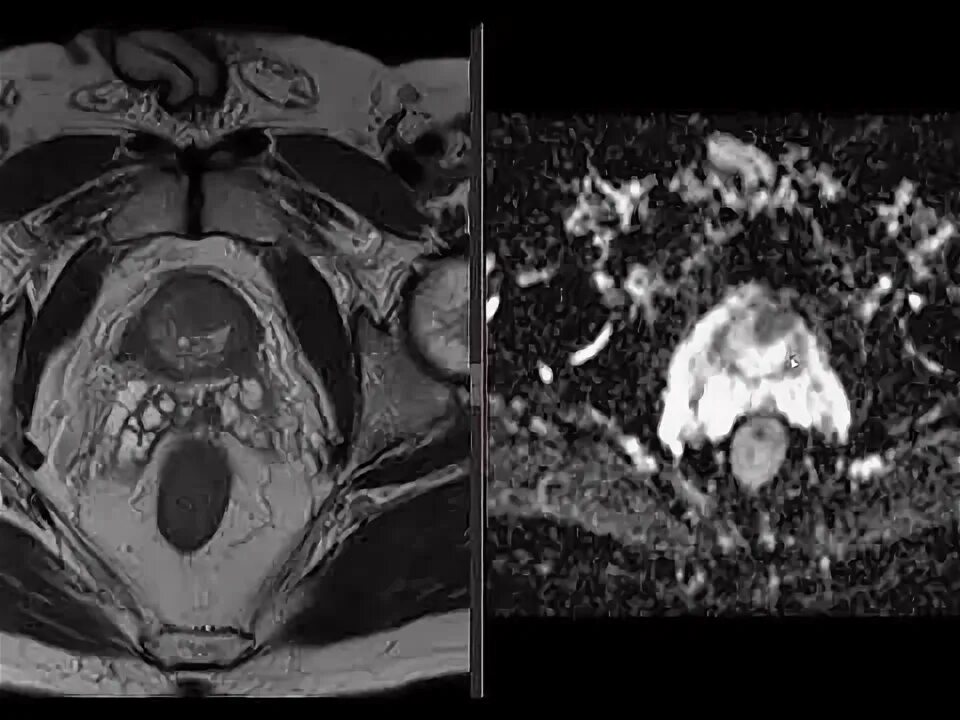

Pi rads v